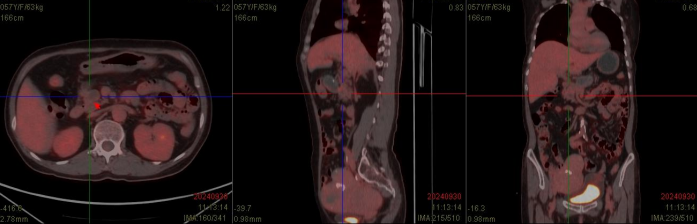

患者为57岁女性,因“发现肝门部占位4月余”来院就诊,住院后完善增强CT、MR检查后考虑肝门部占位为胰头来源肿瘤,囊腺瘤可能,病灶内局部壁结节形成,未排恶变可能,胆总管下段、门静脉、下腔静脉、十二指肠均明显受压。

CT示肝门部肿物,大小约4cm×7cm,位于门静脉及下腔静脉间隙,门静脉、下腔静脉受压。